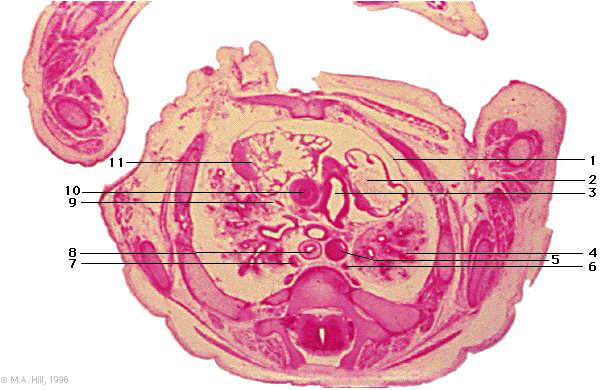

1 |

pericardium |

2 |

left atrium |

3 |

pulmonary trunk |

4 |

lung |

5 |

thoracic aorta |

6 |

hemiazygos vein |

7 |

azygos vein |

8 |

oesophagus |

9 |

superior vena cava |

10 |

ascending aorta |

11 |

right auricle |